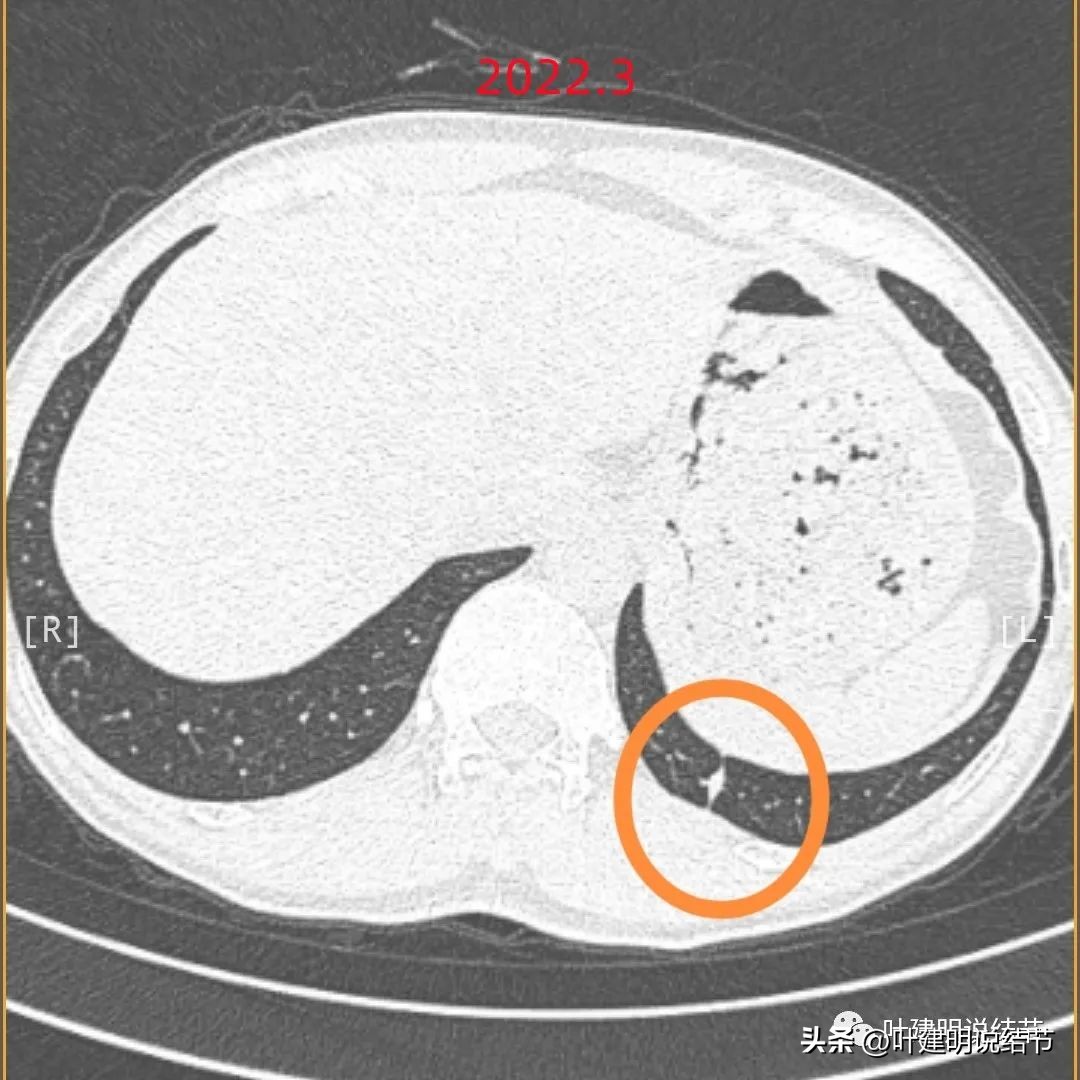

结友提供的影像资料是2022年3月份的,下面是我回复时给他的截图:

当时都没有截图此次手术的病灶,大概因为考虑肯定是局部慢性炎:

好在当时还是建议先半年复查对比下。如果直接告诉结友基本上良性,而他又比较大意,没有半年或一年复查的话,也许结果会有所不同,也存在延误病情的可能性。现在回头再去年主病灶,我把它再截图下来,是下面这样的:

左上细条索状病灶出现

边缘略糊,是条状的。

有个小点状密度较高(粉色箭头),不足5毫米,而且轮廓显糊,边上有条索状。

病灶感觉像慢性炎,轮廓显糊,也不聚在一块。

边缘区域显散在。

胸膜略有异常,但不是牵拉或毛刺的样子(蓝色箭头)。

病灶边缘只是纤维条索状。

上图是当时的CT报告,也是考虑慢性炎。

这样的病灶其实再回头看,仍不首先考虑恶性的,因为整体显糊,也不具明显收缩力,磨玻璃部分散在,更像纤维增生似的。从影像上来看,慢性炎伴纤维增生可能性大。再加上余肺多外结节也是实性的,真的没有恶性的依据。好在一是结友仔细;二是我的建议也比较保守,仍建议他半年复查对比下,如果没有变化再年度复查。